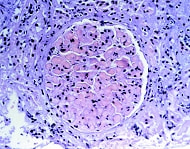

母親が抗リン脂質抗体をもっていると、胎盤の血管に血栓性の梗塞が生じたり、胎児の成長が遅れたり、死亡したり、流産を起こすことがあります。これは、SLEの活動性とは関連しません。

抗リン脂質抗体は血栓を誘発し、血管を詰まらせる作用があるのです。治療は、基本的には少量のアスピリン、プレドニン、ヘパリンを組み合わせて行います(毎日皮下注射、あるいは入院が必要)。